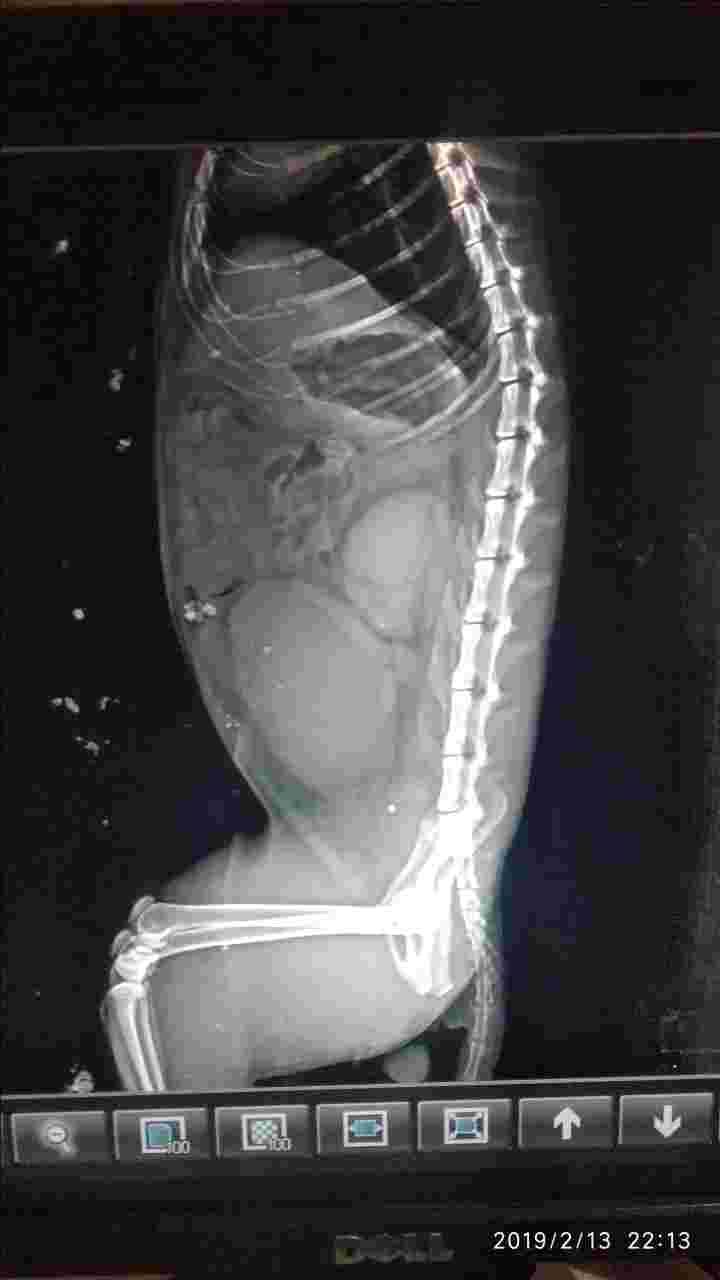

Pet's info: Cat | Persian | Male | unneutered | 3 years and 1 month old | 6.61 lbs

Actually my cat got a knot on his stomach...i was not knowing what happen to him..I took him to a vet and removed xray of it.vet doctor told me that "the knot on his stomach is from the cat food we were giving to the cat.Its meow cat food mackerel adult food.Because of that food my cat got knot on his stomach" thats why doctor told me to we will operate and remove taht knot..but after that operate my cat died.Please ill send you xray pictures..please tell me what was the exact problem to my cat.

I am so sorry for your loss! Without having seen Jack, there is no way I can tell you with 100% certainty what was wrong with him. From JUST looking at these x-rays, it looks like his bladder was blocked (unable to urinate) and there for his bladder got REALLY full and the urine eventually backed up into the kidneys. This likely caused him kidney values to increase and electrolytes to be abnormal. Unfortunately though, I cannot say this for sure and I have no idea if this is what caused him to pass away. I am sorry for your loss and please know you are in my thoughts.